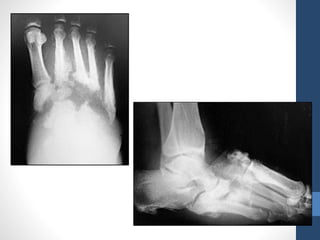

0 1 2 3

Pre or Post

ulcerative

lesion

(epithelialized)

Superficial

(not involving

tendons,

capsules or

bone).

Penetrates to

tendon or

capsule

Bone.

Infection Infection Infection Infection

Ischemia Ischemia Ischemia Ischemia

Infection &

Ischemia

A

B

C

D

University of Texas classification